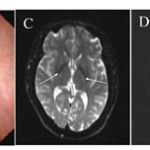

1. Abstract

Cerebrotendinous xanthomatosis (CTX) typically presents with infantile diarrhea, juvenile cataracts, and tendon xanthomas. We report a diagnostically challenging case of late-onset CTX in a 48-year-old male presenting with isolated progressive